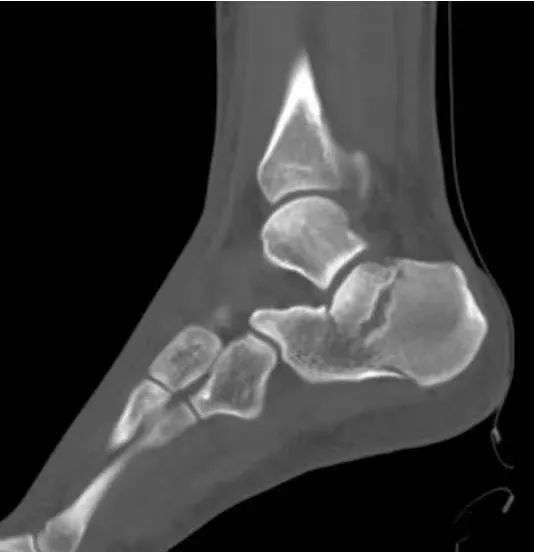

(7)踝部骨折脱位

距骨骨折脱位:多由高处跌下所致,压痛点在距骨,X线片可协助鉴别。

踝部韧带损伤:多由踝关节扭伤所致,肿痛,压痛点在内踝下方或外踝的前下或下方,无骨擦音和畸形;X线摄片可排除骨折。

(8)距骨骨折

踝部骨折:压痛点在内或外踝,有畸形和骨擦音;X线摄片可协助诊断。

跟骨骨折:高处跌下所致,足跟部有瘀斑、压痛,骨折移位严重出现扁平足,后跟增宽;X线摄片可鉴别。

先天性距骨后三角骨:无明显外伤史,多由扭伤踝部照片时发现,照双侧X线片对比多为对称性,三角骨与距骨后侧紧密相连,骨片界线清晰、光滑。